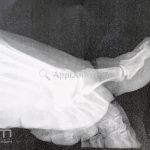

Diagnóstico:

Clínico, radiografia.

RX: proliferação óssea subungueal.